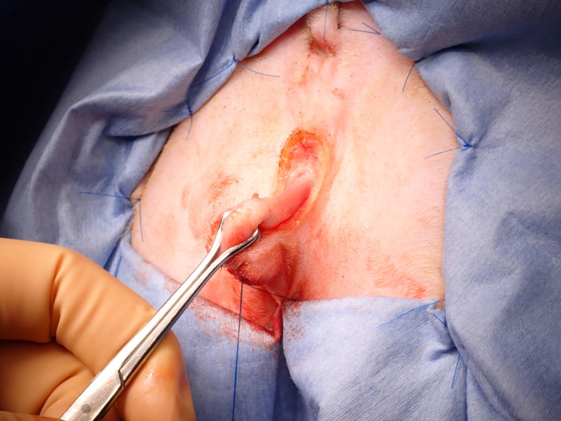

手術中の様子

カテーテルが入ることを確認